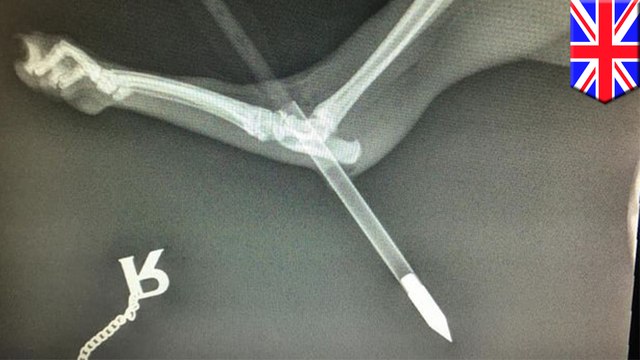

Freak, accident, Flag, launches, soldier, into, falls, feet, survives, TomoNews